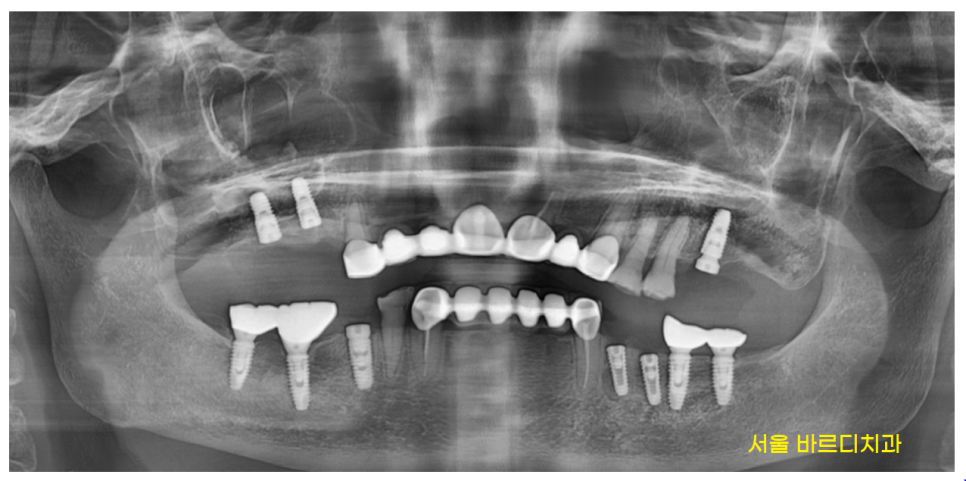

24.02.20

24년 2월에 치료를 끝내드렸습니다.

약 8개월정도 걸렸네요~

환자분께 지금 시작하셔도 내년에 끝난다

말씀드렸었는데

진짜죠~?

임플란트가 뼈와 붙은 시간이 필요해

한두달만에 치료가 완성되는 것이 아닙니다.

벌써 8월도 다 지나가니

지금 명일동 치과에 방문하셔서

수술을 하셔도

아래 어금니는 올해 말

윗니 어금니는 내년 꽃이 필때쯤 마무리가 되겠네요~

▼완성 사진▼